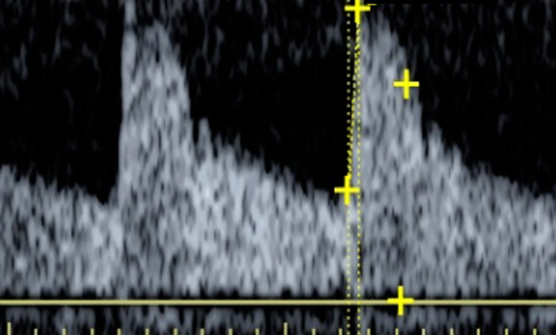

- Ratio of diastolic to systolic blood pressure

- Combined effect of interstitial and venous pressure

- Ratio of lumen area in systole and diastole at the sample site

- Interstitial pressure (increased recoil during diastole if iP raised)